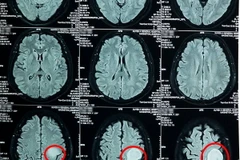

Các bác sỹ Bệnh viện Nguyễn Tri Phương (Thành phố Hồ Chí Minh) đã phẫu thuật thành công cho một bệnh nhân mắc u não, giúp bệnh nhân trở lại với cuộc sống bình thường.

Các bác sỹ Khoa phẫu thuật Thần kinh-Lồng ngực-Bệnh viện Đa khoa tỉnh Thanh Hóa đã cắt bỏ và gỡ dính hoàn toàn khối u ăn sâu vào các cấu trúc mạch máu thần kinh quan trọng của bệnh nhân 63 tuổi.

Các nhà khoa học đã trích một phần khối u của bệnh nhân mắc u nguyên bào thần kinh đệm và sử dụng tế bào này để in mô hình khớp với các ảnh cộng hưởng từ (MRI) của họ.

Bệnh viện Đa khoa Xuyên Á TP.HCM vừa thực hiện phẫu thuật thành công lấy khối u não lớn có đường kính 5cm, tương đương một quả bóng quần vợt ra khỏi não của một nữ bệnh nhân.